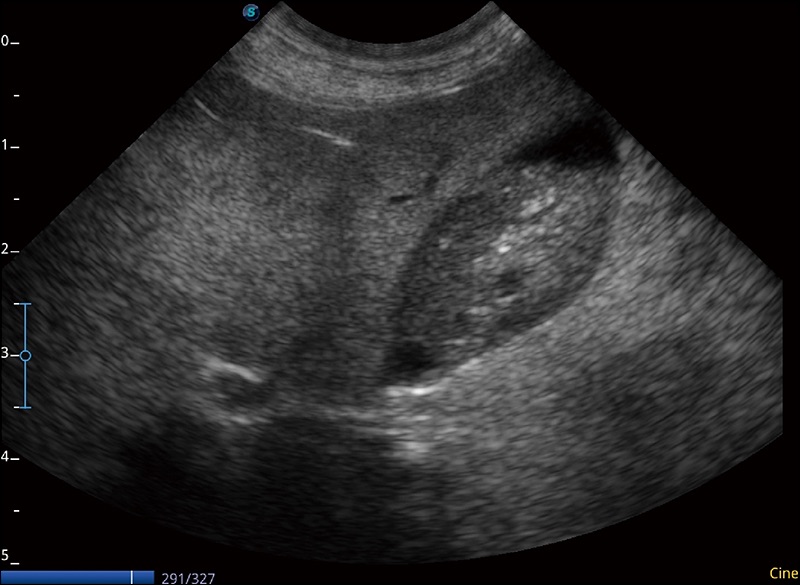

任意波束合成技术

在不牺牲时间分辨率的情况下提供出色的图像

空间复合成像

优化不同角度的图像